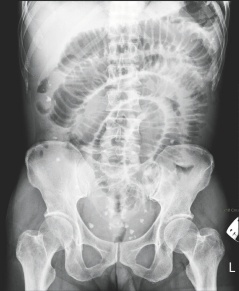

臺(tái)南市55歲女子腹中取出29顆大大小小的“蛋”,從X光上可看到腹中滿布點(diǎn)狀的白色物體。

這名女子最近因腹痛、嘔吐而到成大急診就醫(yī),醫(yī)師從X光檢查中,發(fā)現(xiàn)腹腔內(nèi)有許多白點(diǎn)狀的物體,原本以為是糞石或食物堆積在腸道中,經(jīng)緊急開(kāi)刀,發(fā)現(xiàn)這些物體是在腸子外,而非腸子里,醫(yī)師共取出大大小小共29顆,色白、外形橢圓,很像蛋一般,材質(zhì)卻像橡膠一般有彈性。